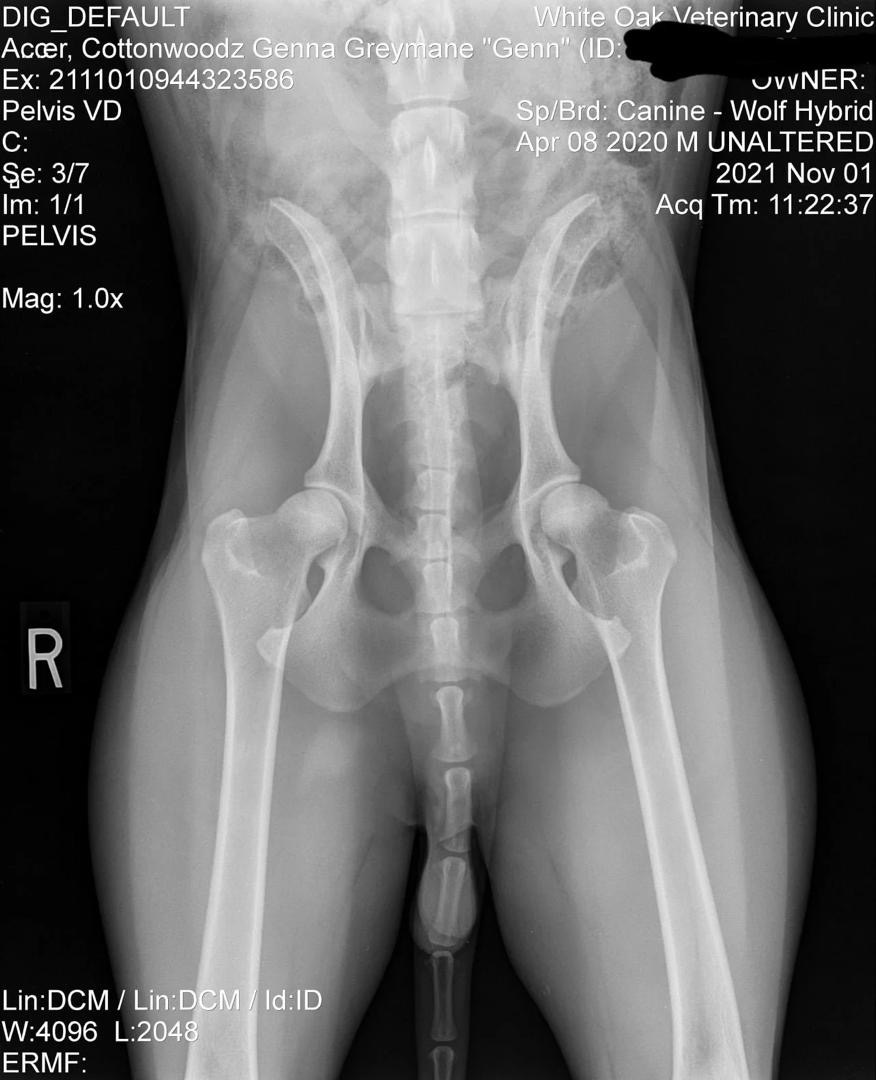

Preliminary Health Screenings

Genn Preliminary Hip X-Ray

Preliminary Hip X-Ray

Early evaluation: Excellent structure